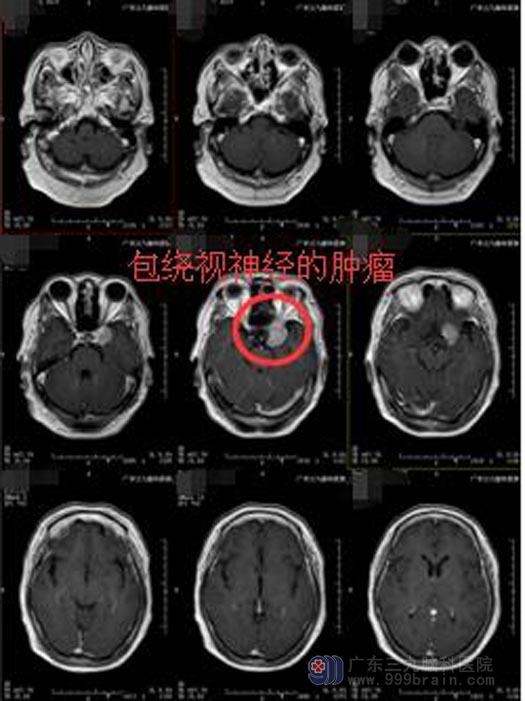

进一步MRI检查结果显示,左侧海绵窦区示一团块状占位性病变,呈T1等T2异常信号,FLAIR序列稍高信号,增强后呈较均匀明显变化并见“脑膜尾”征,大小约2.4cm×1.6×2.2cm,边界清楚,部分包绕左侧颈内动脉、视神经,与左侧大脑中动脉M1段关系密切。诊断为左侧鞍旁海绵窦区占位性病变,考虑脑膜瘤可能。